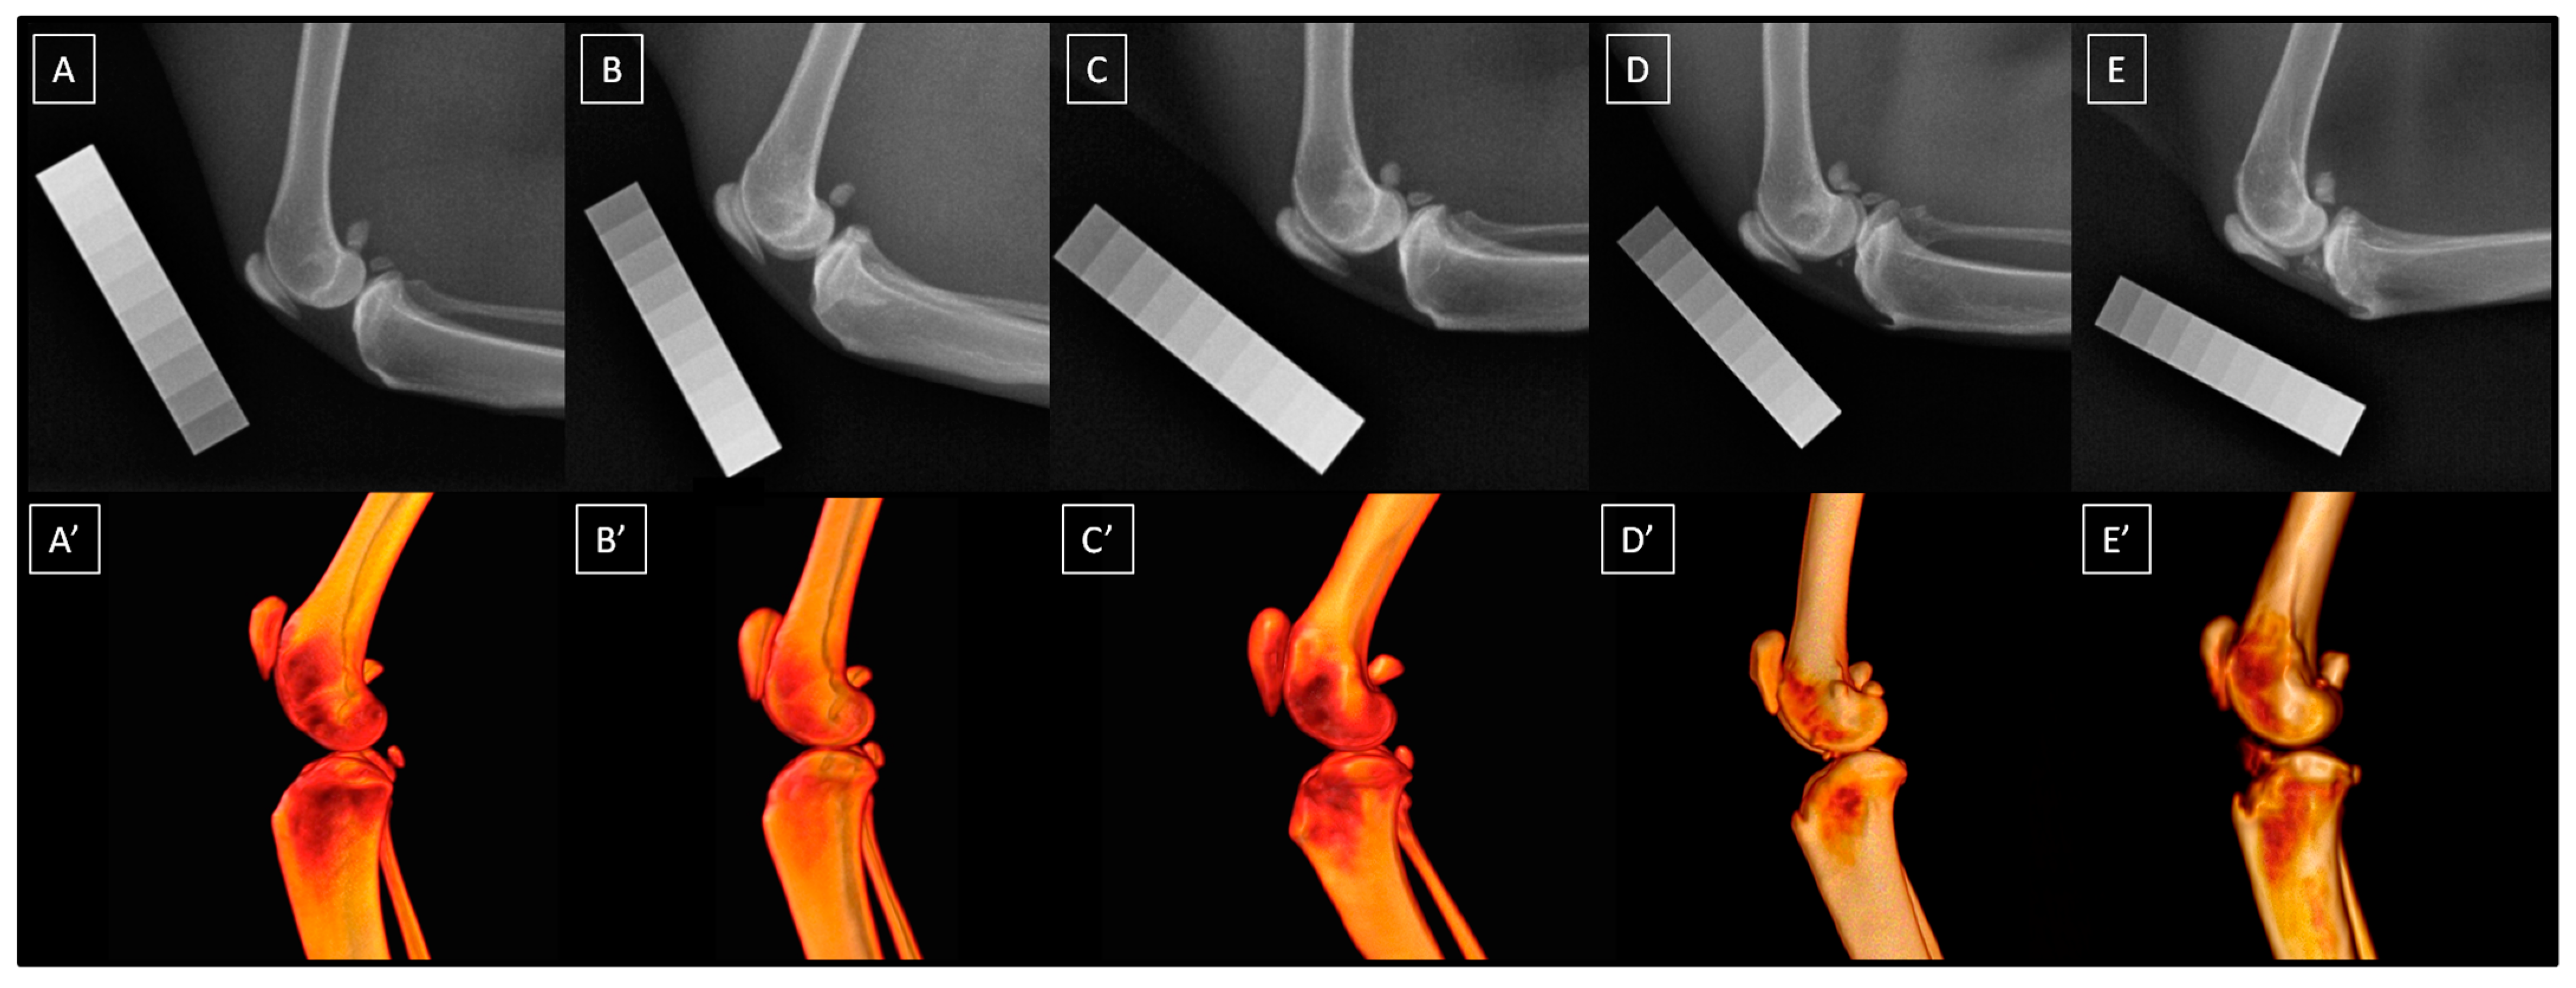

The presence and severity of knee joint OA were assessed radiographically using a 5-point scale (0–4) proposed by Lascelles et al. [5] and described in detail by Bonecka et al. [13]. In this scale, a normal knee joint is assessed as 0, minor OA as 1, mild OA as 2, moderate OA as 3, and severe OA as 4. The scale considers the assessment of joint space (width and shape), cortical bone surface (osteophytes and enthesiophytes), subchondral bone (cyst and sclerosis), periosteal proliferation, and intra-articular mineralization. A detailed description of the radiographic signs for each grade of this 5-point scale can be found in Bonecka et al. [13]. Example radiographs and volume renderings from CT imaging of the same cats for each grade of this 5-point scale are presented in Figure 2. Cats were imaged until at least five knee joints were classified as belonging to each of the five OA-related groups. Once this limit was met, the recruitment of new individuals ceased.

Figure 2.

The radiographs (A–E) and volume renderings (A’–E’) of feline knee joints are classified as follows: a normal joint (A,A’), minor osteoarthritis (OA) (B,B’), mild OA (C,C’), moderate OA (D,D’), and severe OA (E,E’).